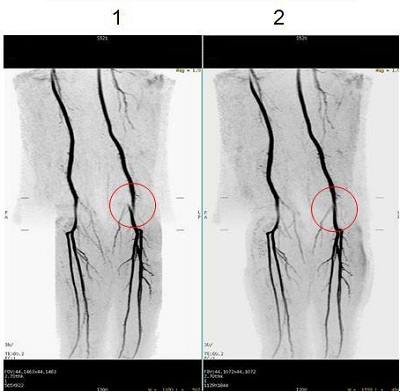

Figure 1. 3D Inhance Deltaflow acquisitions

Table 1. Image legend

NumberDescription

1Image acquired with 3D Geometry Correction Off.

2Image acquired with 3D Geometry Correction On.